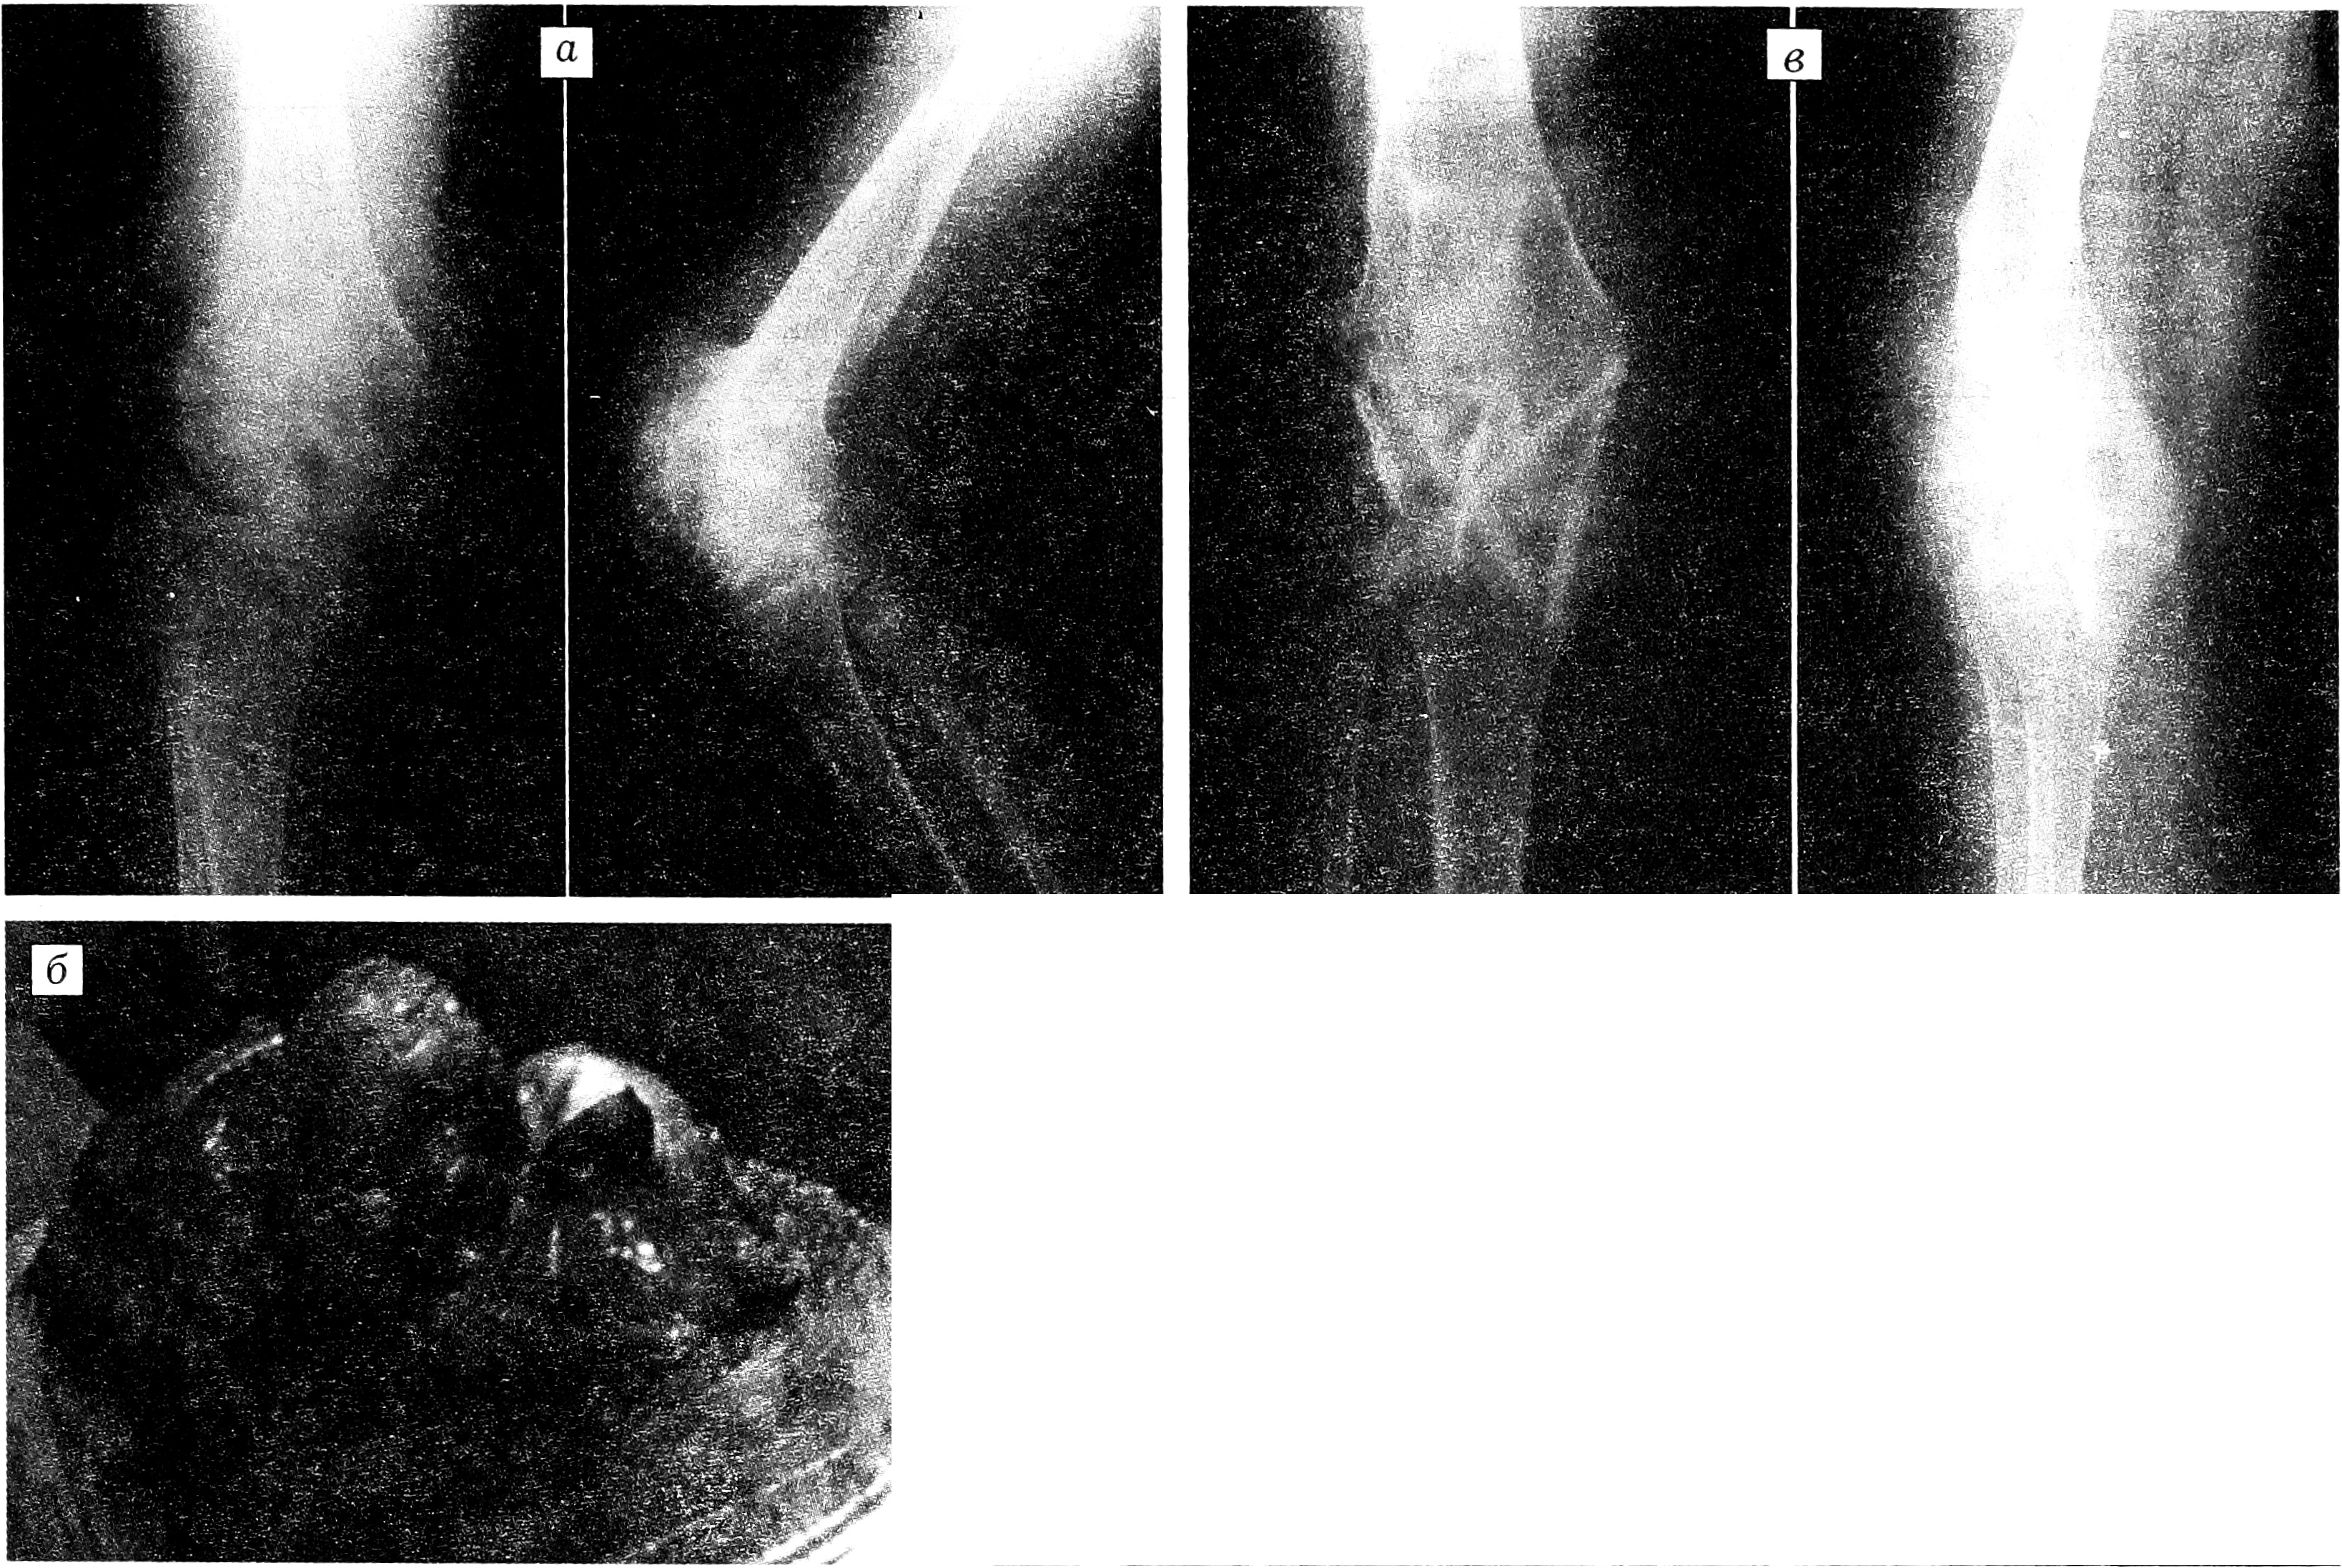

Рентгенологически, как правило, выявлялась асимметрия эпифиза: пораженная половина его была массивной, увеличенной в объеме, причудливо деформированной, имела неоднородную структуру с участками обызвествления. В ряде случаев обнаруживались свободно лежащие внутрисуставные тела. Последнее время в диагностике ГЭД мы используем компьютерную томографию, которая позволяет, помимо структурных изменений пораженной кости, определить взаимоотношение патологических и здоровых тканей (рис. 1).

Рис. 1. Больной 6 лет с гемимелической эпифизарной дисплазией таранной кости.

a — рентгенограммы голеностопного сустава в прямой и боковой проекции; б — компьютерная томограмма.

При поступлении ось правой нижней конечности нарушена за счет стойкой болевой контрактуры в коленном суставе под углом 90°. Контуры сустава сглажены, сустав резко увеличен в объеме, деформирован. Кожные покровы над ним гиперемированные, лоснящиеся, теплее, чем на здоровой стороне. Движения в суставе отсутствуют. На уровне нижней трети правого бедра определяются патологическая подвижность, крепитация. Сосудистых и неврологических расстройств в правой нижней конечности не выявлено. На рентгенограммах обнаружен винтообразный перелом нижней трети правой бедренной кости со смещением отломков. Наружные мыщелки бедра и большеберцовой кости значительно увеличены, причудливо деформированы, неоднородной структуры, с участками обызвествления. Зоны роста нитевидные, местами закрытые (рис. 2, а). Нарушений со стороны внутренних органов не выявлено. Анализы крови и мочи в пределах возрастной нормы.

Рис. 2. Больной С. 13 лет с гемимелической эпифизарной дисплазией дистального эпифиза большеберцовой кости.

а — рентгенограммы коленного сустава в прямой и боковой проекции при поступлении: виден перелом нижней трети бедренной кости; б — патологические разрастания пораженных эпифизов (во время операции); в — рентгенограммы коленного сустава через 5 мес после операции.

Через 2 мес перелом сросся, и 14.04.97 было произведено хирургическое вмешательство. Во время операции обнаружены костно-хрящевые разрастания, исходящие из дистального эпифиза бедренной и проксимального эпифиза большеберцовой кости, размером 4×6 и 5×7 см, резко деформирующие суставные поверхности (рис. 2, б). Надколенник не был изменен, под ним в проекции межмыщелкового возвышения находилось свободно лежащее округлое костно-хрящевое образование диаметром 3 см. Произведены резекция коленного сустава, удаление патологических тканей, артродез с использованием кортикальных аллотрансплантатов.

Послеоперационный период протекал без осложнений, рана зажила первичным натяжением. Гипсовая иммобилизация продолжалась 5 мес. Контрольный осмотр: артродез состоялся (рис. 2, в), однако имеется укорочение правой ноги на 5 см, что требует дальнейшей ортопедической коррекции. Наблюдение за больным продолжается.